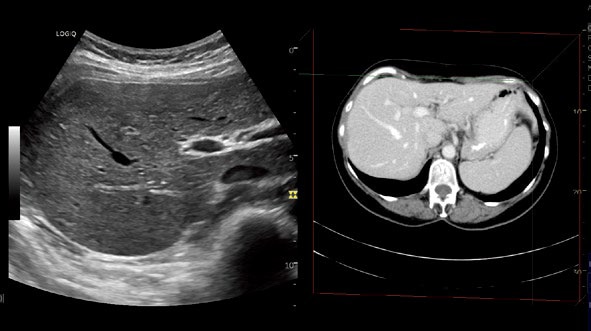

Compare Assistant

過去画像をRAW Dataで保存してあれば、

スキャン条件を一致させて検査中の画像と比較可能です。

Vnav Import

他モダリティのVolume Dataを読み込み可能です。

病変部の客観的な把握をサポートします。